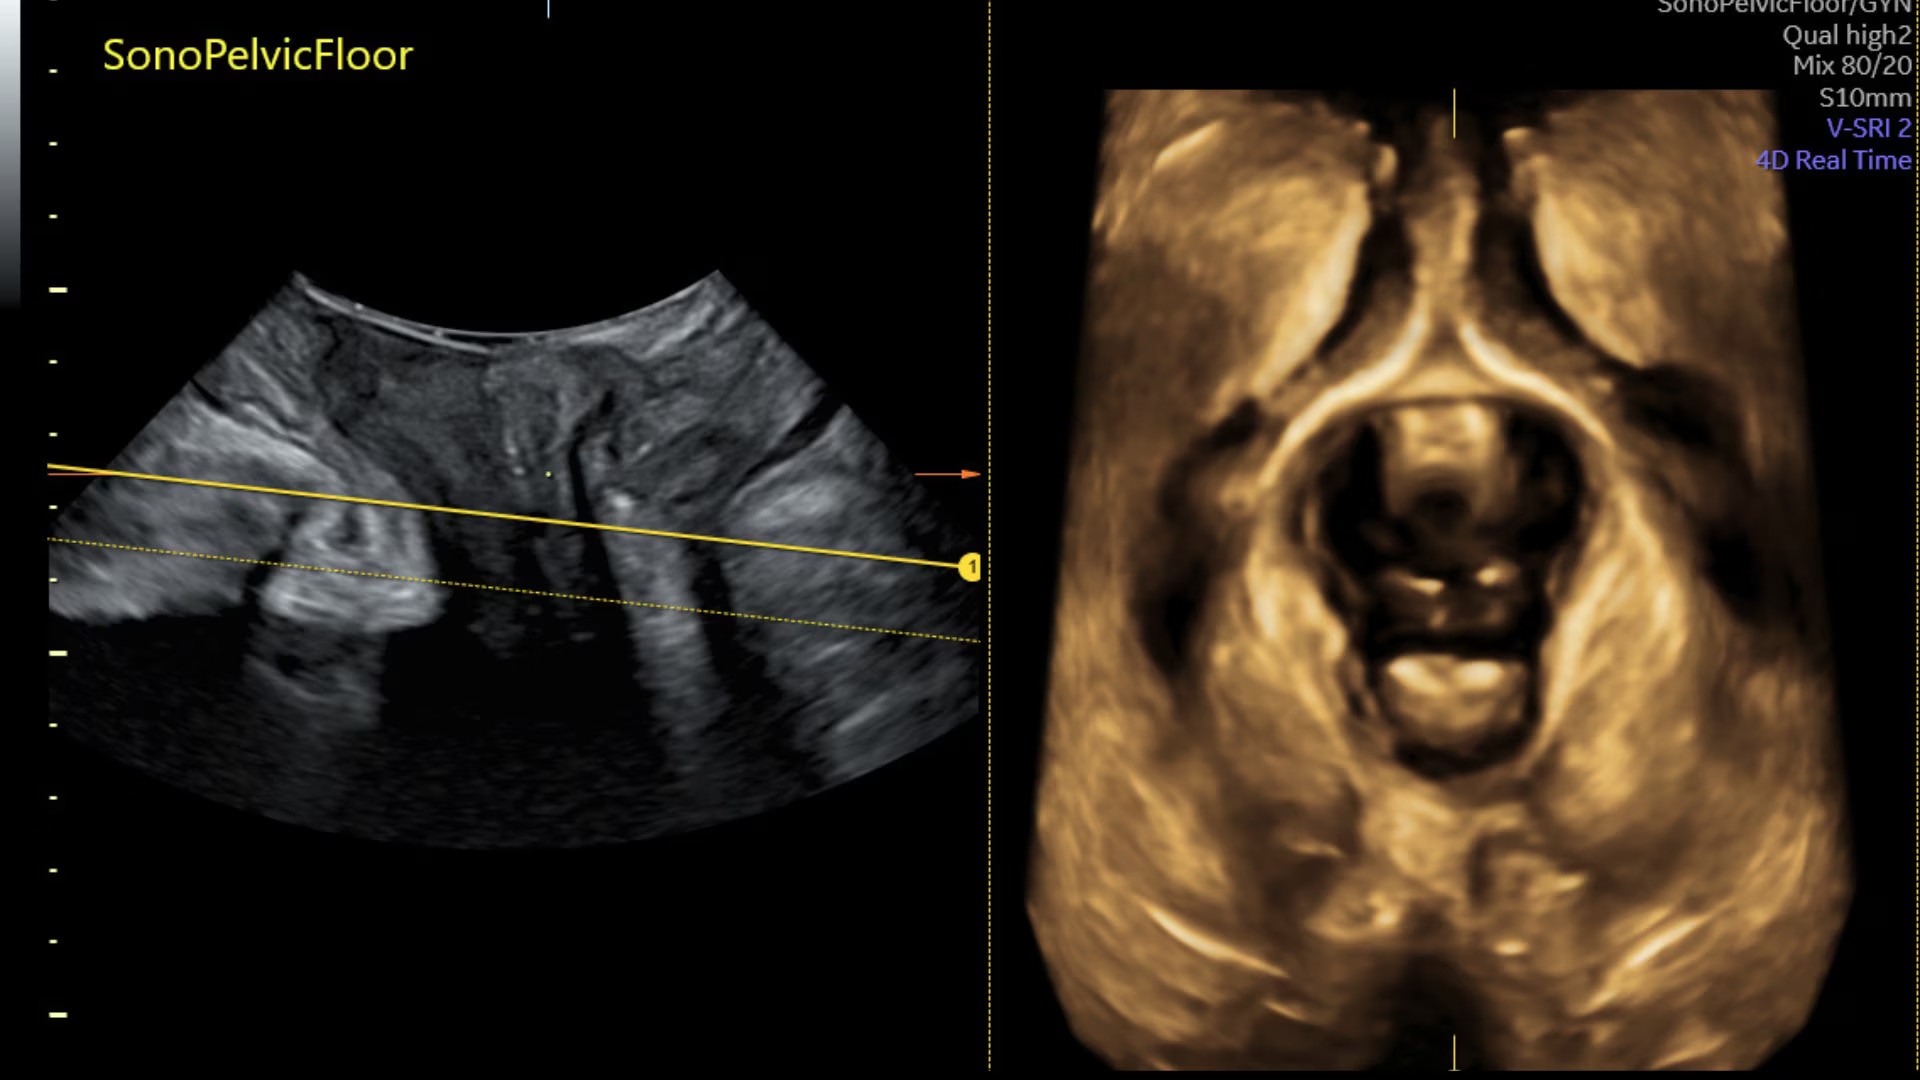

Sonopelvicfloor

Assess pelvic floor anatomy using guided workflow & AI

Using a guided workflow and AI, SonoPelvicFloor:

• removed exam complexity by automating plane alignment and measurements

• can reduce keystrokes by up to 75% and offer users a time savings of up to 80%